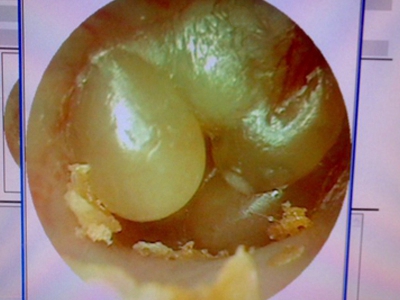

鼓膜炎又称为大疱性鼓膜炎,是鼓膜和邻近鼓膜的外耳道皮肤的急性炎症。由病毒感染所致,多发生在儿童和青年人,多为单侧,冬季多见。根据有感冒史、耳痛的症状及检查所见,容易诊断。

鼓膜炎的首发症状为外耳道剧痛,并可有轻度听力下降。随后,由于大疱破裂而有稀薄血性分泌物从外耳道流出;由于病变限于鼓膜的上皮层,未波及纤维层,故大疱破裂后无鼓膜穿孔。